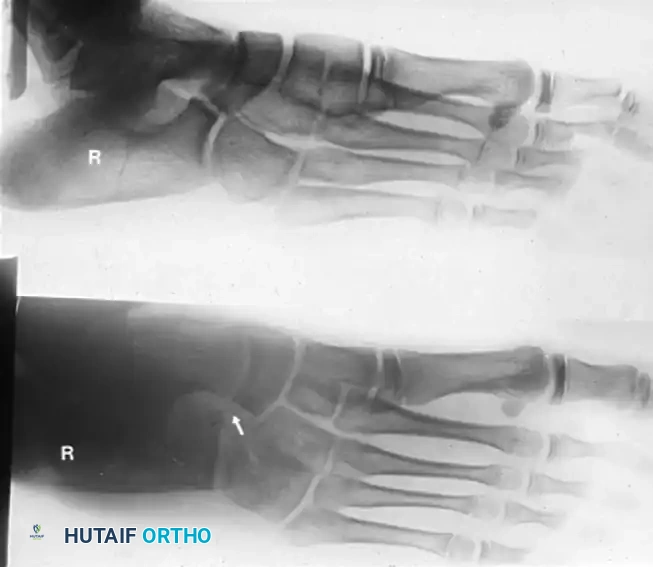

Thorough radiographic evaluation is mandatory before proceeding with a calcaneonavicular bar resection. Standard weight-bearing anteroposterior, lateral, and oblique radiographs of the foot should be obtained. The 45-degree internal oblique view is the gold standard for visualizing a calcaneonavicular bar, which will appear as a solid bony bridge or an irregular, sclerotic pseudoarticulation between the anterior process of the calcaneus and the navicular.

- Verification of Resection: We strongly recommend a lateral oblique radiographic examination on the operating table after resection to confirm adequate removal. Usually, a 1.5- to 2.5-cm segment of the bar must be removed. Ensure that the lateral fourth of the articular surface of the talus is left uncovered by the navicular; this serves as an anatomic landmark confirming adequate excision.